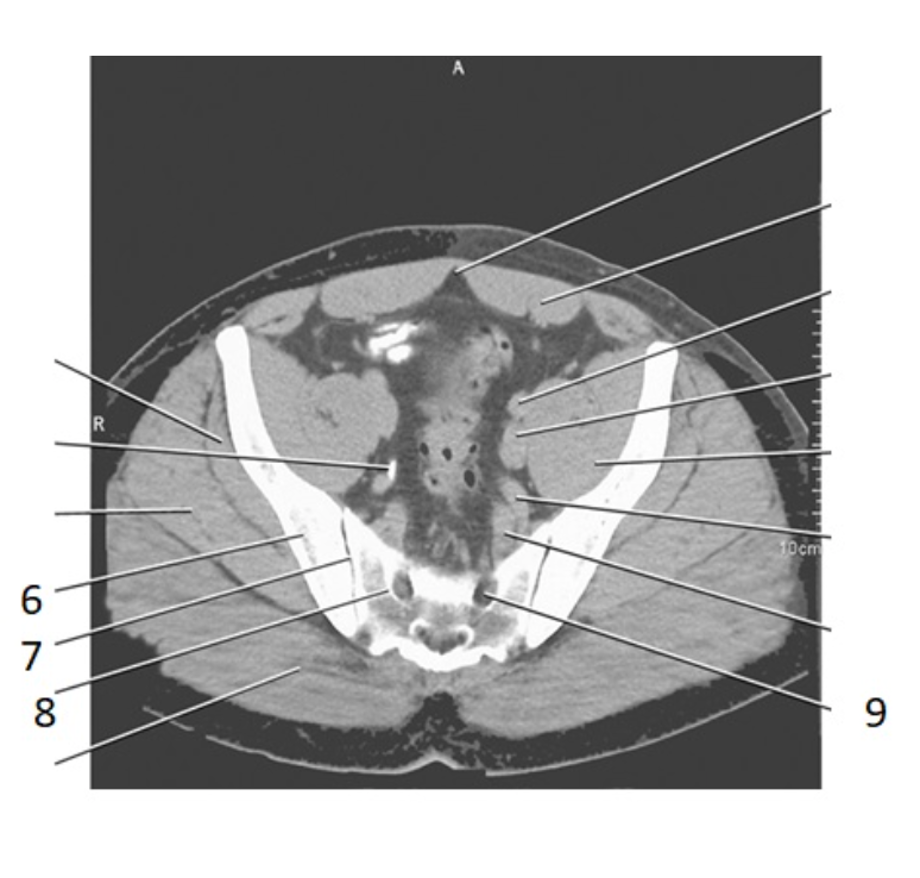

6

ilium

8

psoas

9

sacram foramen

7

SI joint